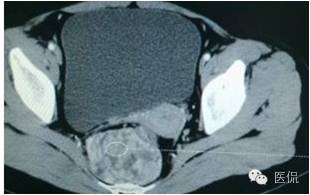

增强延迟期(CT值106HU)

结果

手术是:盆腔占位,病理为:血管肌纤维母细胞瘤。与肛门粘连,于是同时做了肛门的处理。